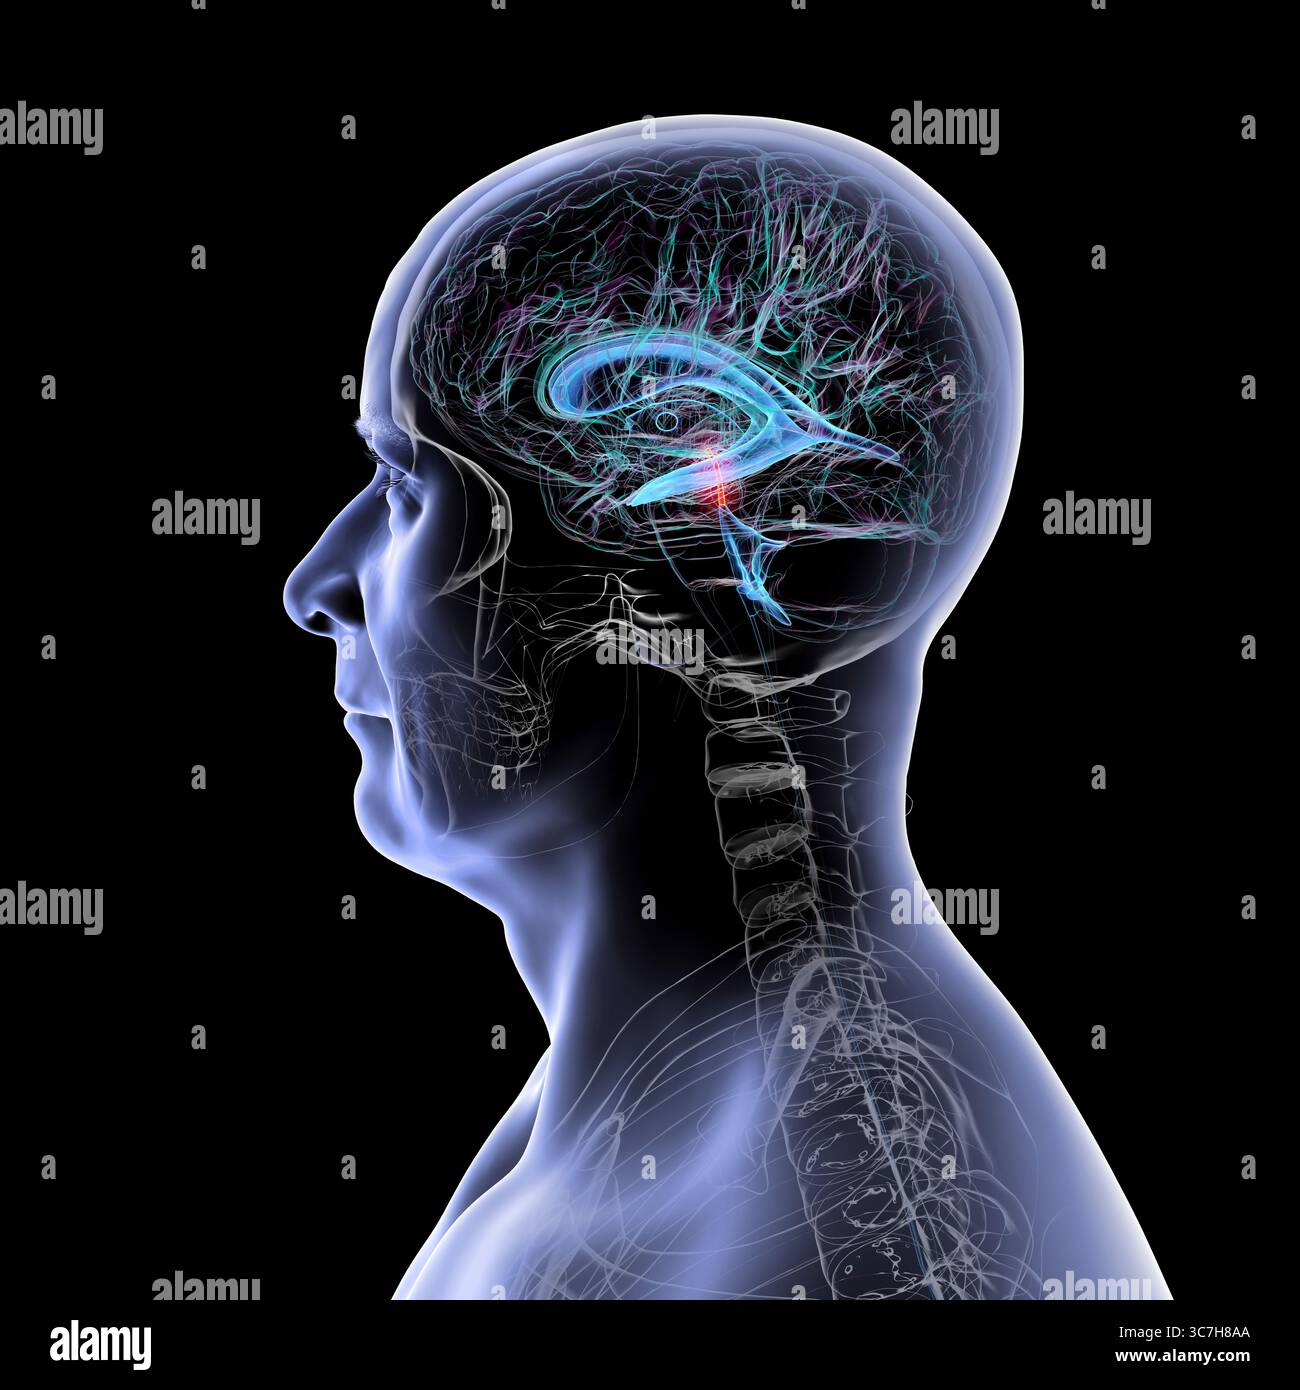

RF3C7H8A8–Abbildung des Gehirns mit hervorgehobenem Aquädukt (rot) und ventrikulärem System (blau), Darstellung des Liquorflusses.

RF3C7H8A6–Abbildung des Gehirns mit hervorgehobenem Aquädukt (rot) und ventrikulärem System (blau), Darstellung des Liquorflusses.

RF3C7H8AA–Abbildung des Gehirns mit hervorgehobenem Aquädukt (rot) und ventrikulärem System (blau), Darstellung des Liquorflusses.

RF3C7H8AF–Abbildung des Gehirns mit hervorgehobenem Aquädukt (rot) und ventrikulärem System (blau), Darstellung des Liquorflusses.

RF3C7H8A3–Abbildung des Gehirns mit hervorgehobenem Aquädukt (rot) und ventrikulärem System (blau), Darstellung des Liquorflusses.